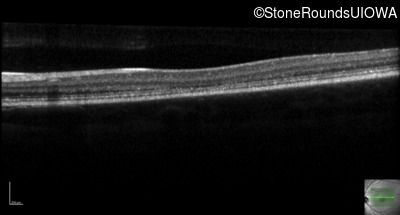

Age at visit: 13 years

This 13 year old male first had difficulty reading print and road signs in the past year.